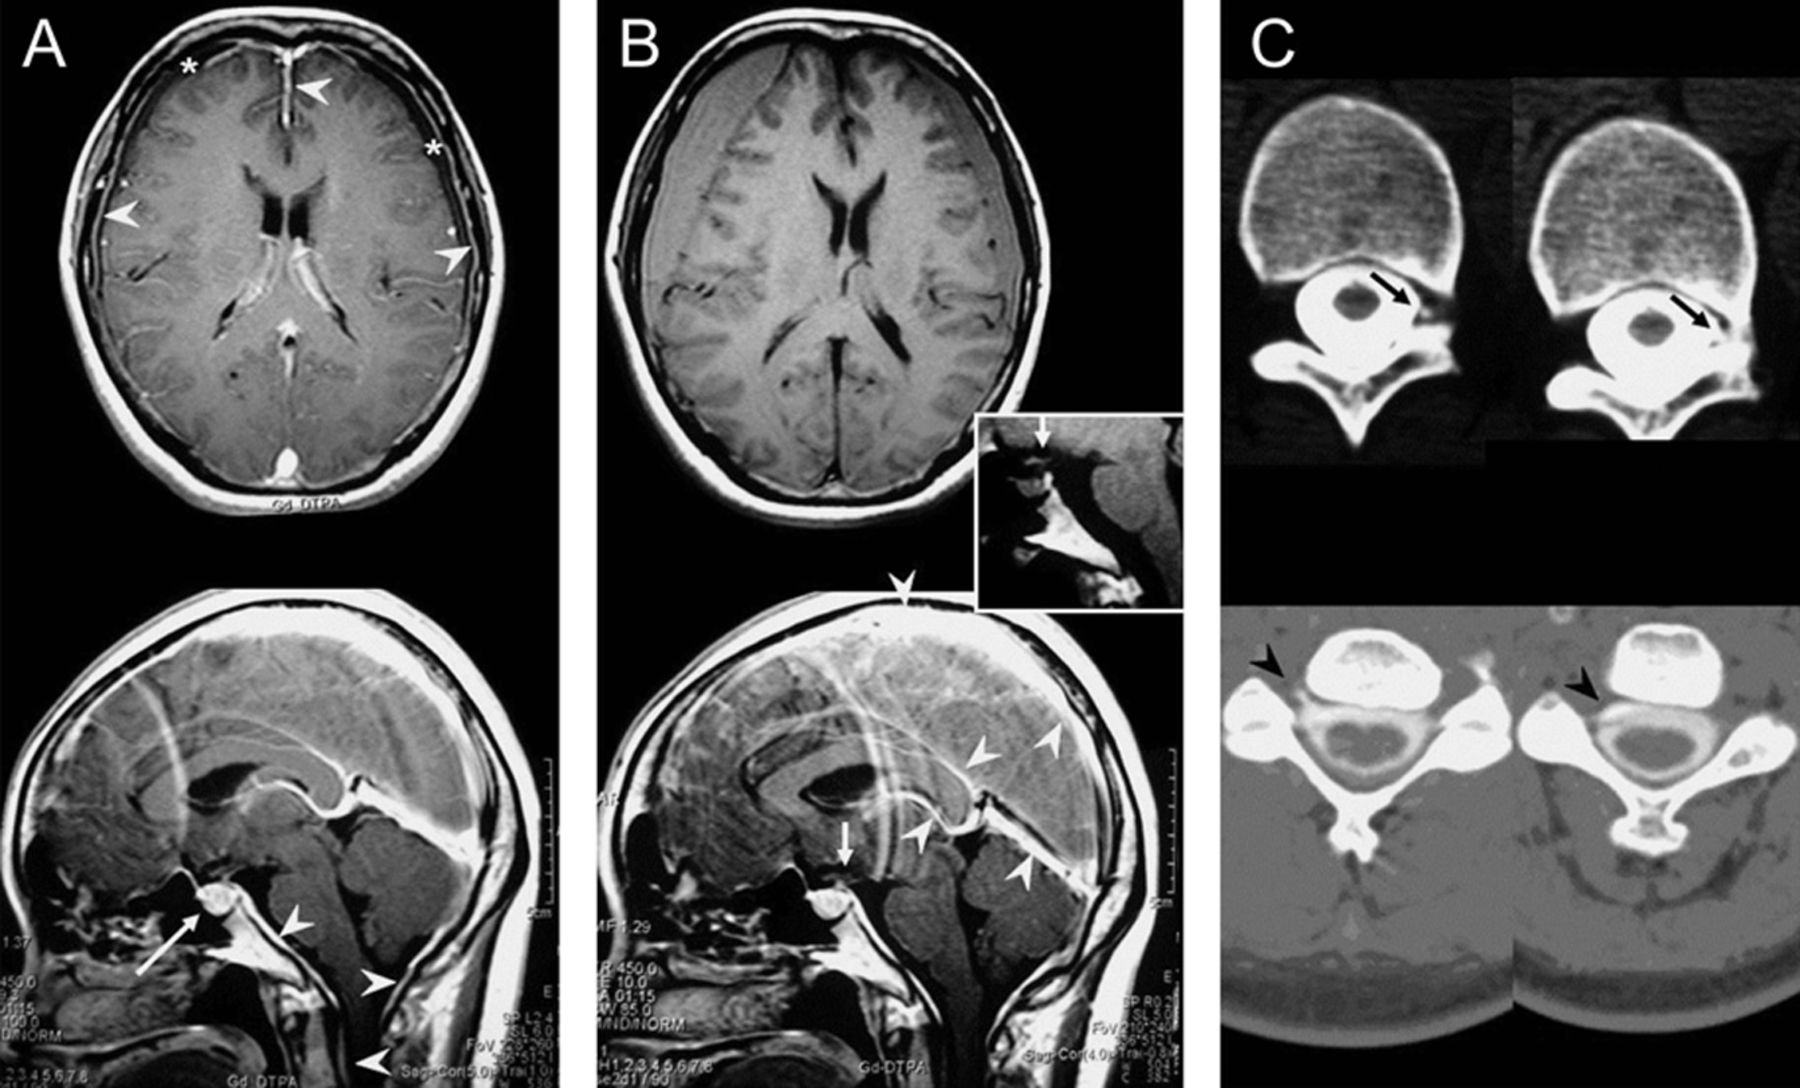

教学神经图片:硬脑膜下血肿pseudo-intracranial高血压

一个40岁的女人面对恶化的头痛伴有呕吐,厌食,耳鸣。头痛最初直立的。MRI显示慢性进行性硬膜下血肿(SDH)重大质量效应,扩散pachymeningeal增强,增强垂体/扩大(图中,A和B),表明颅内低血压由于自发脊髓脑脊液漏,CT证实的脊髓造影术(图中,C)。SDH的脑脊液漏是一个重要的原因,1通过临床和影像学表现,可能会给病人颅内高血压的假象,但没有视神经乳头水肿或脑积水,称为pseudo-intracranial高血压。这一认识是至关重要的因为保守措施,降低颅内压和疏散SDH是有害的。1,2

(一)承认,post-gadolinium t1加权磁共振成像显示硬膜下血肿(SDH,星号),pachymeningeal增强(箭头)和垂体增强/扩大(箭头所指)。(B)两周后卧床休息和水化,pre-gadolinium(上部面板和插图)和post-gadolinium(下图)t1加权磁共振成像显示压缩的SDH的发展正确的侧脑室,从右到左的中线移位,并向下位移的光学仪器(箭头),但pachymeningeal增强和提高垂体/扩大暗示脑脊液体积损耗由于脑脊液漏仍然可以看到post-gadolinium图像(下图)与pre-gadolinium相比图像(插图)。还要注意最小静脉结构的改善充血(箭头)保守治疗后,建议持续脑脊液漏。(C) CT脊髓造影术显示低压H(40毫米2O)和多个CSF漏T11-12(上部面板、箭头)和C4-5(降低电池板,箭头)的水平,随后接受硬膜外血补丁。